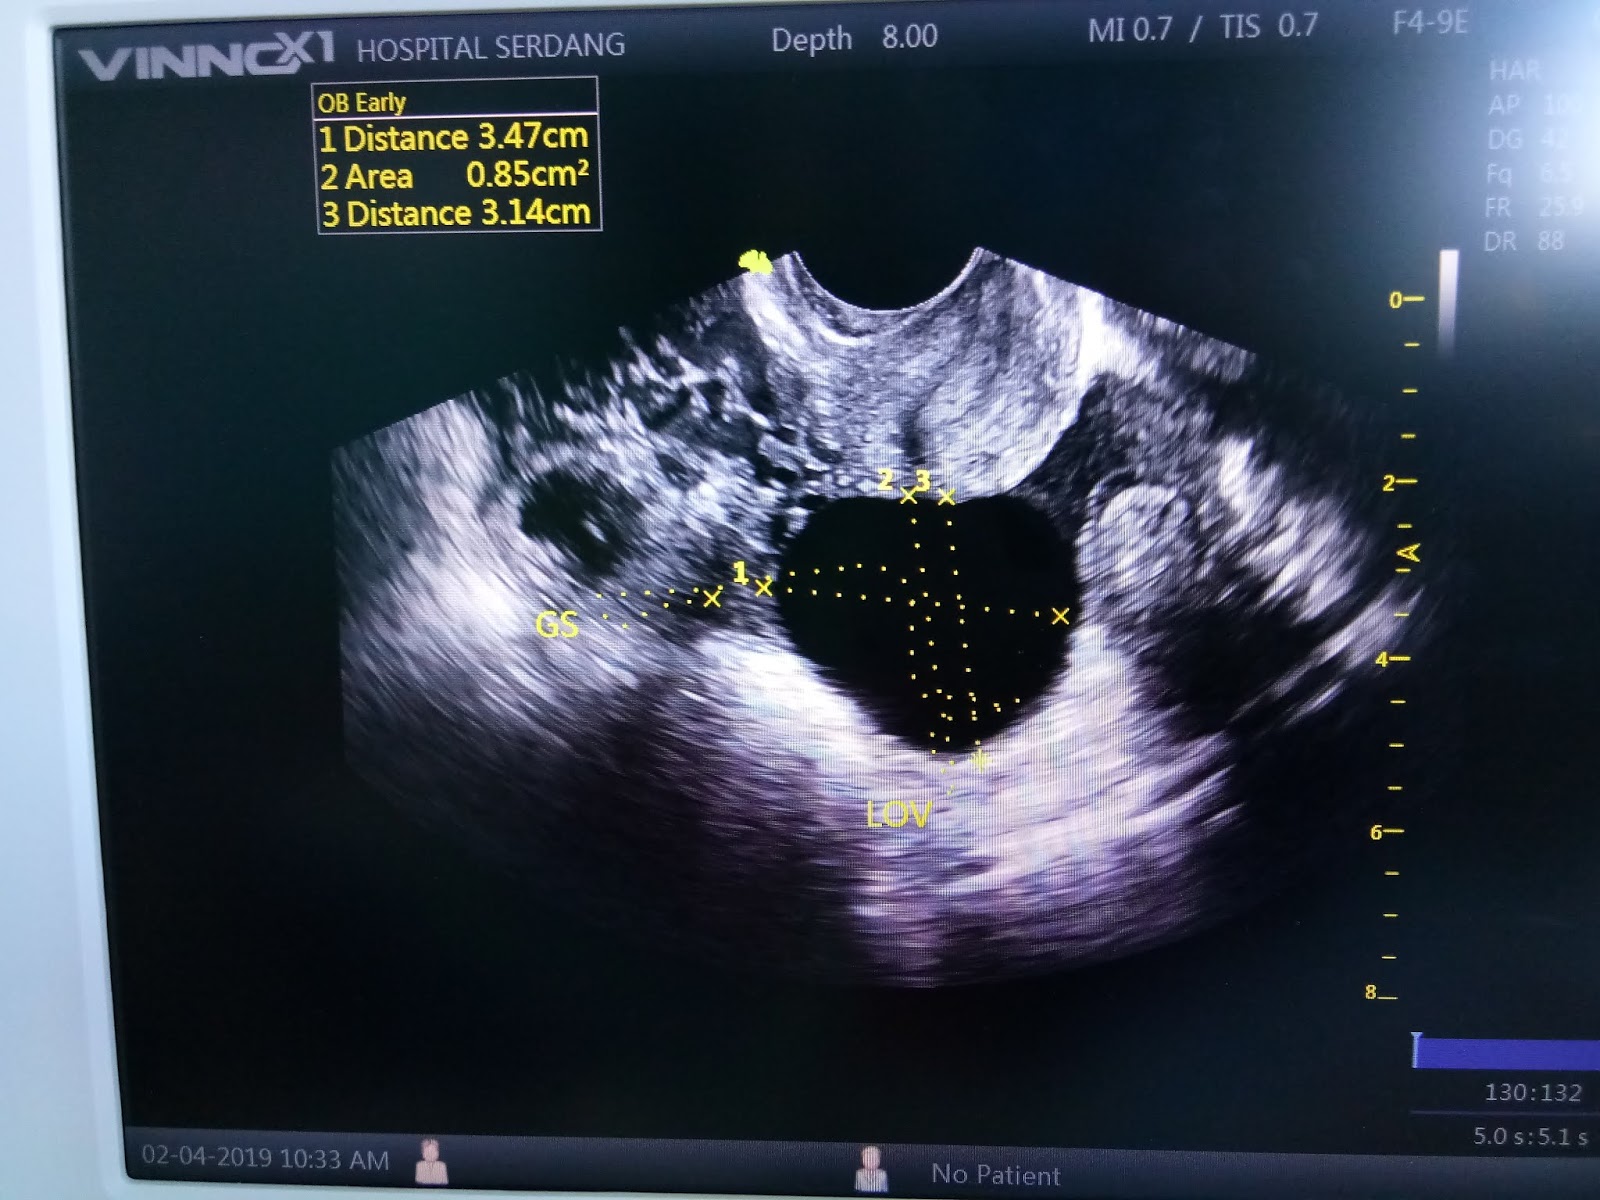

- Berbekalkan referral letter and BHCG result test, terus serbu wad kecemasan. Dalam referral letter tu (Lupa pulak nak ambil gambar), dia just mention yang dia tak jumpa baby. So aku terus masuk wad kecemasan, terus cakap saya mengandung tapi tak jumpa baby and kemungkinan ectopic. And pagi tu rasa sakit tu macam kerap sangat pulak datang, so jalan pon dah slow je. So macam biasa la government, akan buat saringan dulu, lepas tu tunggu nombor ape semua and terus je refer ke Gynae. Alhamdulillah mudah dan cepat sangat untuk urusan pagi tu. Selalu orang cakap government lambat kan. Tapi pagi tu ya Allah mudah and cepat je settle semua benda. So sampai kat gynae, dapat doctor perempuan Alhamdulillah. Sangat baik and kelakar.

Kena scan thru vagina, Again!

And tarraaa. Sekejap je dah dapat result!

yang left side, kecik tu, is the baby, which is outside rahim, the right side yang besar tu is the cyst.

- Memula doctor perempuan tu scan, dia nak confirmkan pon macam berani tak berani. Dia nak panggil pakar dia dulu datang and buat confirmation. And doctor tu lelaki berbangsa Cina. Andddd, memang confirmed. Ectopic pregnancy. Doctor Cina tu sangat baik and explain details gila pasal ectopic ni. Dia explain pasal procedure, effects and macam macam lagi. And terus admitted. Aku? Dah takde air mata dah nak nangis. Memang macam dapat agak ectopic. Btw baby masa ni dia hidup tau. Tapi kena buang sebab tak berada dia tempat yang sepatutnya. So aku rasa macam dah banyak buang masa, duit, tenaga dekat hospital private tu. Cane laaaaa kau buat keje kan. Geram je bila ingat balek.

- Bila dah transfer ke ward balik, nurse pon cakap 'Puan, waktu makan dah takde ye, Puan call suami puan mintak hantarkan makanan. Ni handphone puan' Aku mintak tolong dia cajkan phone. Baik gila nurse ni dia tolong carikkan charger dalam beg aku yang ada macam macam barang tu and cajkan terus. Nasib baik suis tu kat atas kepala je. So terus call husband bagitau dah siap and mintak hantarkan bubur dengan ikan bilis sebab lapar sangat. Tak lama lepas tu terus aku tertido balek. Sebab memang akan rasa nak tido je. Tiba tiba ada doctor datang kejut and tanya keadaan macam mana. Rupanya dia yang bedah aku. Dia pon selak baju kat perut and explain yang dia cucuk 4 lubang. 1 lubang untuk masukkan camera (area pusat). Ni nama dia laparoscopy. Yang lagi 3 lubang tu dia masukkan tools untuk remove segala benda. So dia bagitau aku, yang baby tu memang membesar dekat aku punya left fallopian tube. And fallopian tube tu dah berdarah siket so dia kata dia terpaksa remove sekali fallopian tube tu sebab kalau simpan memang takkan berfungsi lagi dah and nanti lagi bahaya sebab takut infection. So sebab tu aku rasa sakit perut belah kiri. Tapi dia cakap fallopian tube kanan aku normal so should be no problem untuk get pregnant again. Pasal cyst pulak, dia kata bila masuk camera, dia tak jumpa cyst tu kat mana. So dia kata, pasal cyst tu tak payah risau sebab mungkin dah tak aktif.